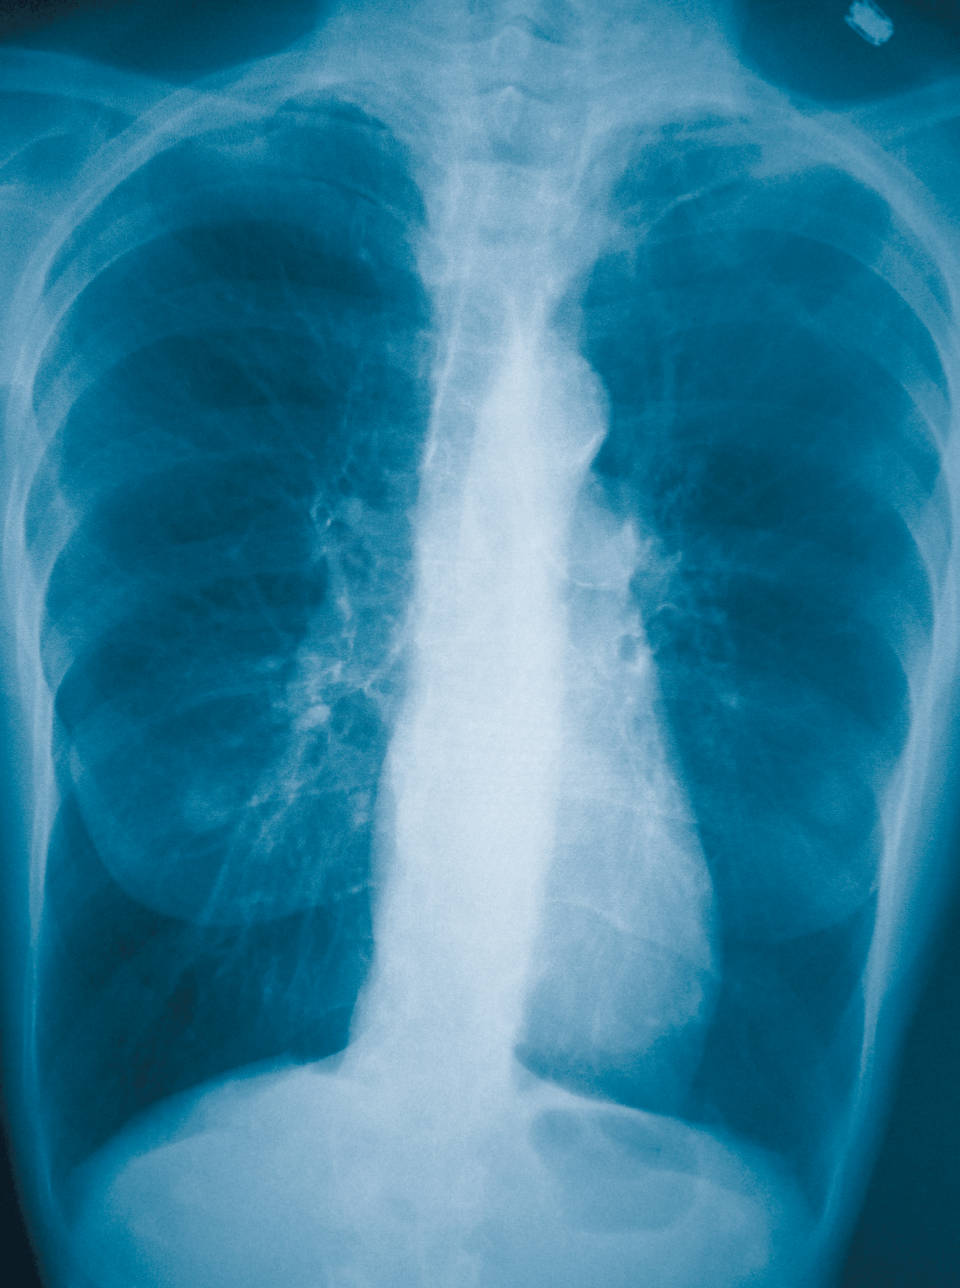

Haben wir in der Vergangenheit COPD falsch therapiert? Prof. Dr. med. Adrian Gillissen, Direktor Medizinische Klinik III, Klinikum am Steinenberg/Ermstalklinik, im Interview. Haben wir in der Vergangenheit COPD falsch therapiert? Prof. Dr. med. Adrian Gillissen, Direktor Medizinische Klinik III, Klinikum am Steinenberg/Ermstalklinik, im Interview. © wikimedia/James Heilman/MT-Archiv

Im letzten Jahr brachte die FLAME-Studie inhalative Kortikosteroide (ICS) in der COPD-Behandlung in Verruf. Doch aufgrund dieser Ergebnisse die ICS gleich zu Grabe zu tragen, wäre falsch, meint Professor Dr. Adrian Gillissen im Interview mit Medical Tribune.